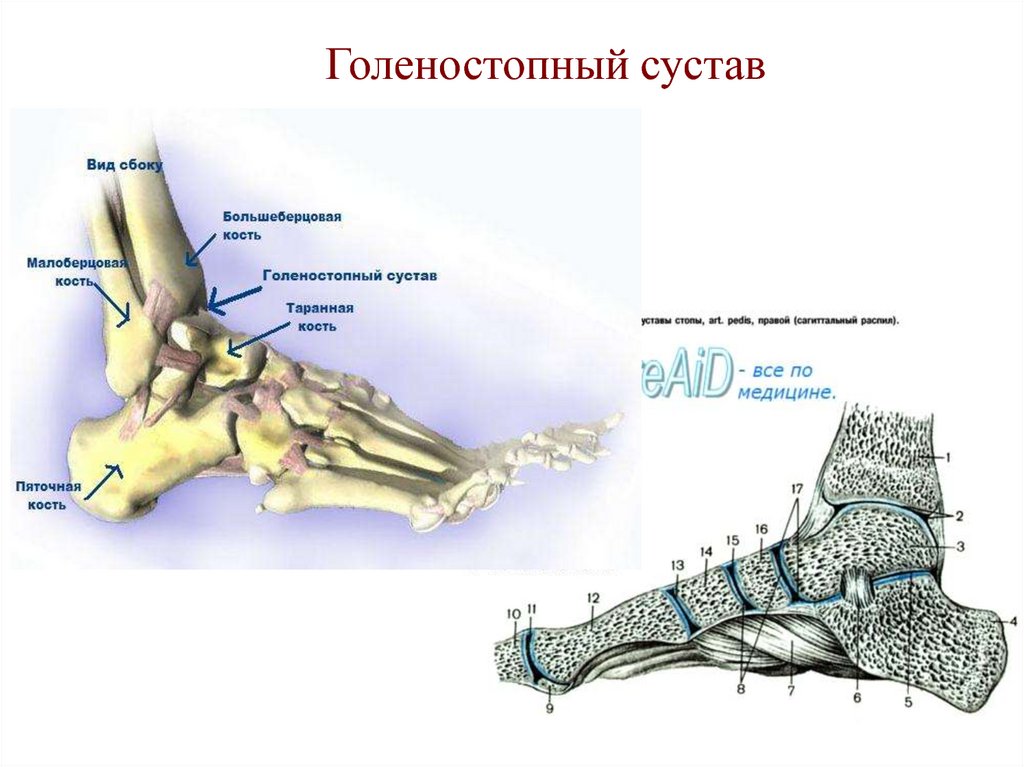

Анатомические фото голеностопного сустава и его суставных поверхностей